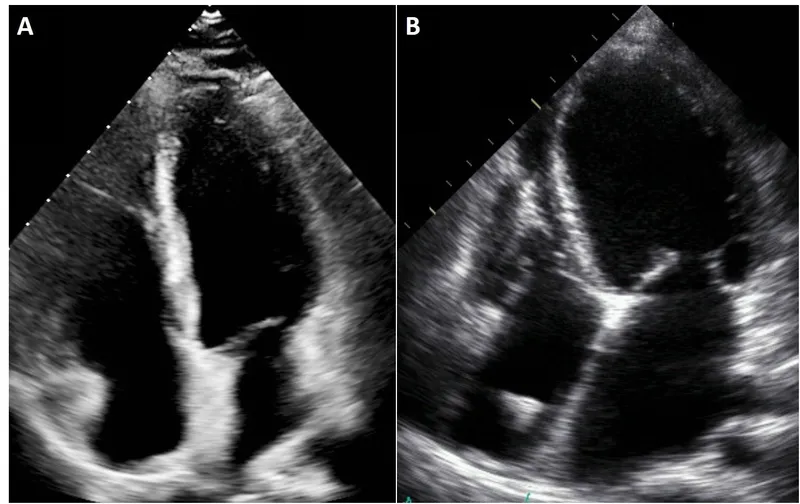

A 68-year-old woman presents with 20 minutes of crushing central chest pain radiating to her left arm, associated with nausea and sweating. Your immediate ECG shows 3 mm ST elevation in leads V2-V4. This is an anterior STEMI requiring immediate catheter lab activation within 120 minutes of first medical contact. Contrast this with the 55-year-old man with exertional chest tightness relieved by rest: you arrange CT coronary angiography as first-line investigation per NICE CG95, which has 95% sensitivity and 83% specificity for obstructive coronary disease. demands troponin measurement at 0 and 3 hours (high-sensitivity assays), while requires NT-proBNP followed by echocardiography within 2 weeks if >2000 pg/mL or 6 weeks if 400-2000 pg/mL. diagnosis relies on echocardiographic criteria: severe aortic stenosis defined as valve area <1.0 cm², mean gradient >40 mmHg, or peak velocity >4.0 m/s.

| Heart failure | NT-proBNP >2000 pg/mL (urgent echo within 2 weeks) | 1.5% adults |